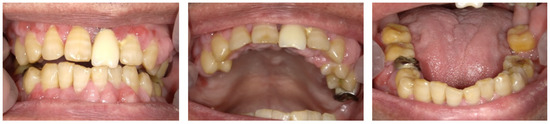

2.3. Day 14 and Later